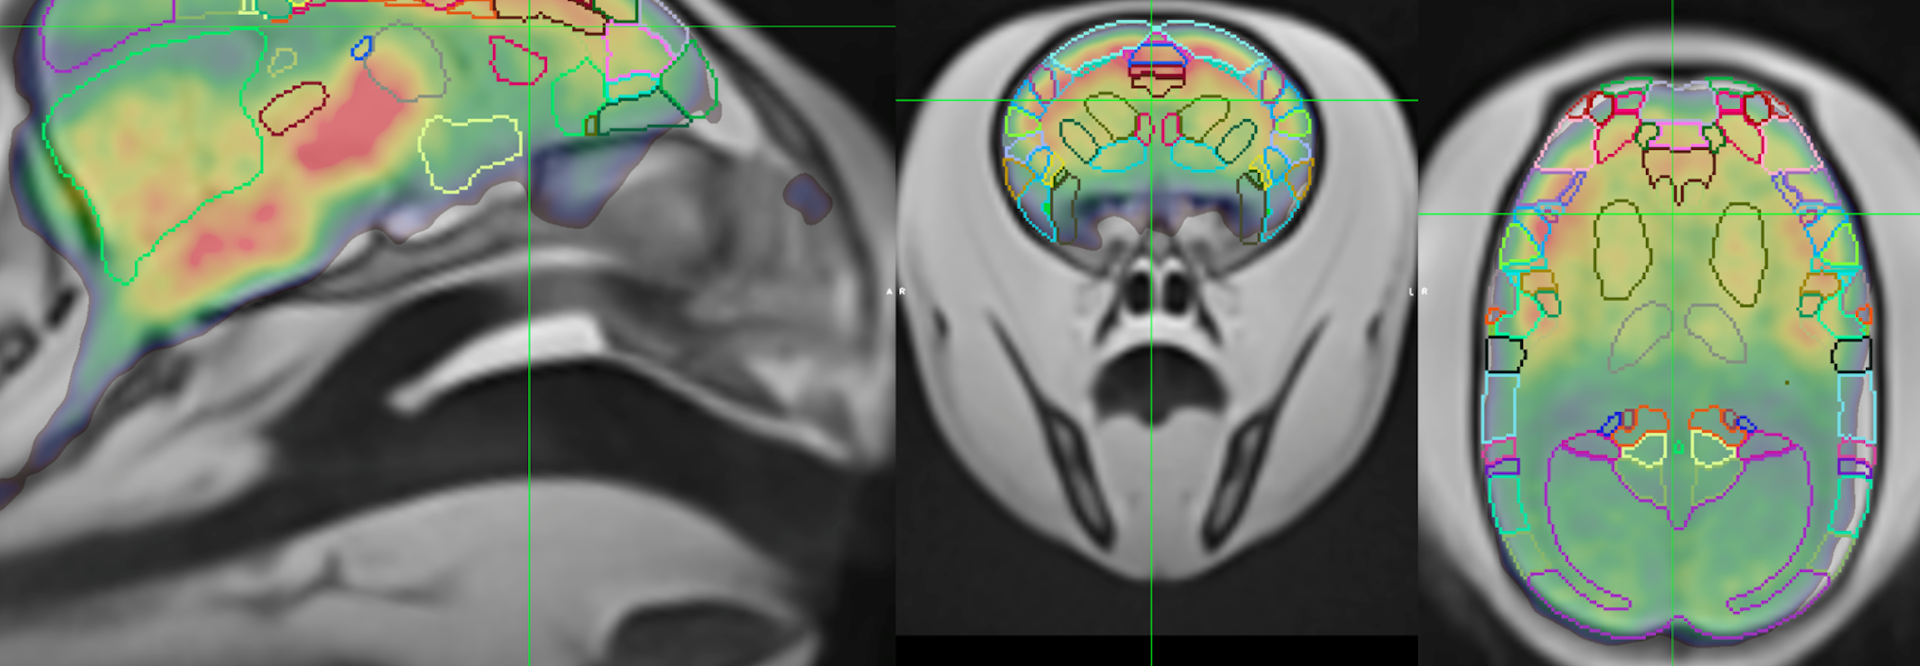

PET/CT and MR Neuroimaging Methods to Study Alzheimer’s Disease

We are working to establish the marmoset as the first primate-specific model to reveal the earliest cellular and molecular events of AD processes and allow charting of AD progression from its inception. We believe that the simultaneous assessment of genetic, molecular, functional, behavioral, and pathological phenotypes in marmosets will provide translatable knowledge of the origins and progression of AD in human populations. In this webinar, I will describe our use of multimodal neuroimaging techniques to evaluate AD-related phenotypes in our marmoset AD models, carrying all imaging in conscious, fully awake animals, thus avoiding the confounds of anesthesia.